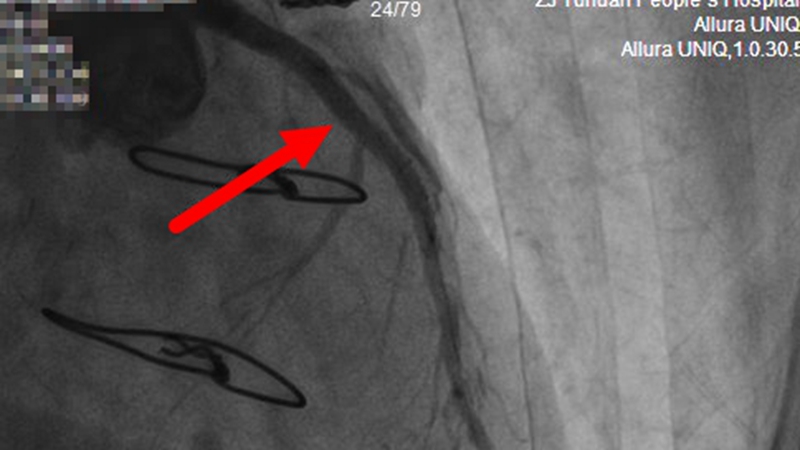

【前降支近段植入支架,血管恢复正常直径】

桥梁堵塞无法再通,那就另寻他路。救心团队当机立断,果断决定翻修老路,在5年前就闭塞掉的前降支近段植入支架。

桥血管闭塞后介入手术是介入治疗中非常高危的手术之一!危急时刻,救心团队顶住巨大压力,凭借高超技艺,最终成功开通血管,惊险战赢死神。